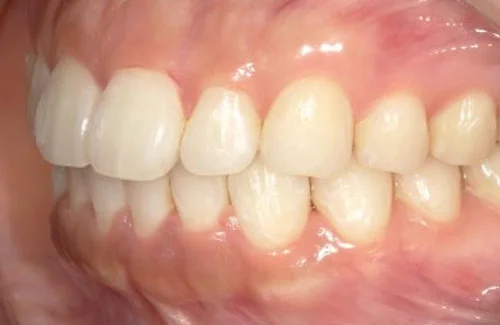

<症例7>歯がガタガタで噛み合わせが悪くお悩み

抜歯無し・マウスピースのみで矯正した症例です。

もともと歯列弓が非常に狭く、V字に近い形をしていたので噛み合わせも非常に不安定でした。

また、下顎前歯部がかなり上の方に生えていたため、下の前歯が上の前歯を突き上げてしまい出っ歯の状態になっていました。

現在では見た目はもちろん、臼歯の噛み合わせも改善しております。

患者様と症状

主訴:歯のガタガタ、噛み合わせが悪い

性別・年齢:20代女性

問題点:叢生(重度)、V字歯列弓、ディープバイト

診断:前歯部の叢生を伴うアングルⅠ級、骨格性Ⅰ級の不正咬合

主なリスク:臼歯の移動に伴い一時的に咬合しにくくなる、歯肉退縮

症状:叢生(そうせい) 過蓋咬合(かがいこうごう)

治療内容

治療期間:1年10ヶ月

治療費用:990,000円(税込)

プラン:Full2プラン

抜歯:無し

再診治療費:無し

追加治療費:無し

保定装置費:無し

治療前後の写真